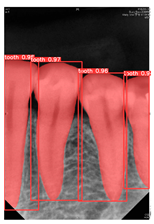

After training the YOLOv8 detection model, this study used an untrained test dataset for accuracy prediction and evaluated accuracy through the confusion matrix, as shown in Equation (5). The validation results are presented in Table 5, where the accuracy of the YOLOv8 detection model with CLAHE enhancement reached 97.01%, significantly higher than YOLOv7’s 95.37% and YOLOv5’s 90.59%. This indicates a notable improvement of the YOLOv8 model over its predecessors.

The YOLOv8 model was used to predict the unmarked and untrained original test dataset, with the prediction results shown in Table 7. The evaluation was conducted using the Precision–Recall curve, as shown in Figure 11. The Precision–Recall curve illustrates the model’s precision and recall at different IOU thresholds. In Figure 11a, when the IOU equals 0.5, the mAP reaches 0.989. Additionally, the closer the curve is to the upper right corner of the coordinate axis, the better the model’s performance in correctly identifying samples. The F1–Confidence curve shows the variation of the F1 score at different confidence thresholds, with the highest F1-score of 0.97. The Precision–Recall curve of this study is very close to the upper right corner, indicating that the model has high precision and high recall.